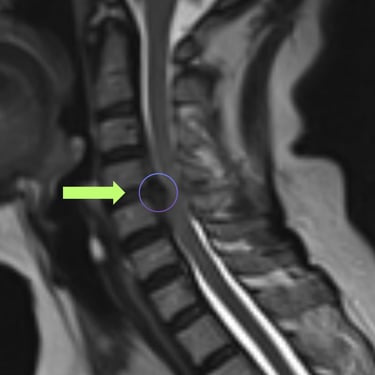

La hernia cervical es una causa frecuente de dolor en el cuello, hormigueo en los brazos y debilidad muscular. Cuando el tratamiento conservador no alivia los síntomas, la cirugía de discectomía cervical con artrodesis (ACDF) se convierte en una excelente alternativa. Este procedimiento consiste en retirar el disco dañado que comprime los nervios y reemplazarlo con un injerto o prótesis que estabiliza la columna. La ACDF ofrece alta tasa de éxito, mejorando el dolor, la fuerza y la calidad de vida. Gracias a técnicas modernas y una recuperación controlada, muchos pacientes vuelven rápidamente a sus actividades habituales.